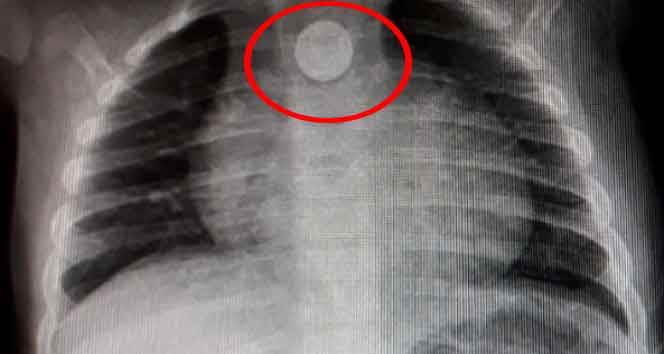

Bursa'nın İnegöl ilçesinde evinde oynarken yerde bulduğu madeni 1 lirayı yutan 9 aylık bebek ölümden döndü. Röntgen filminde bebeğin boğazındaki 1 lirayı farkeden doktorlar operasyonla parayı çıkardı. Evine dönen Mustafa ise her şeyden habersiz oyunlarına devam etti.

Bozuk para röntgen filminde ortaya çıktı

Yoğun bakıma alınan minik bebeğe önce film çekildi. 9 aylık Mustafa'nın boğazına takılan madeni para filmde ortaya çıkınca doktorlar tarafından operasyon yapıldı. Boğazındaki 1 lira çıkarılan minik bebek daha sonra rahat nefes almaya başladı. 1 gün hastanede müşahade altında tutulan küçük çocuk bugün taburcu edildi. Doktorların zamanında müdahalesiyle yeniden hayata dönen küçük çocuğu evinde yeniden oyuncaklarıyla oynamaya başlaması ev sakinlerini sevindirdi.